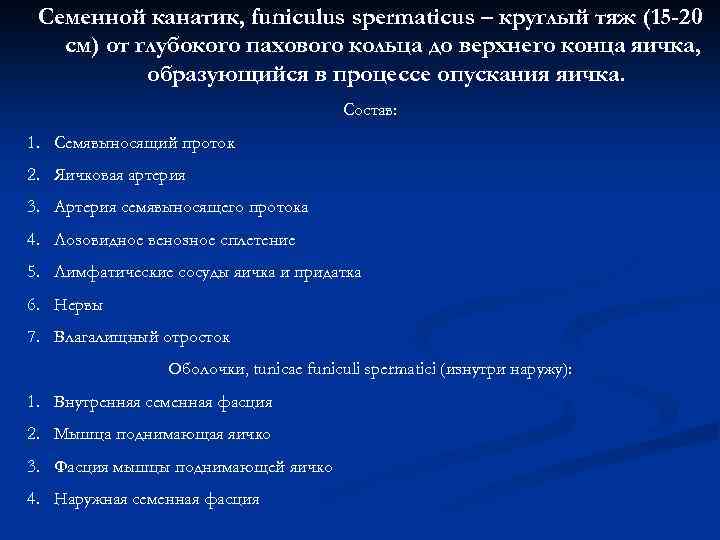

Семенной канатик, funiculus spermaticus – круглый тяж (15 -20 см) от глубокого пахового кольца до верхнего конца яичка, образующийся в процессе опускания яичка. Состав: 1. Семявыносящий проток 2. Яичковая артерия 3. Артерия семявыносящего протока 4. Лозовидное венозное сплетение 5. Лимфатические сосуды яичка и придатка 6. Нервы 7. Влагалищный отросток Оболочки, tunicae funiculi spermatici (изнутри наружу): 1. Внутренняя семенная фасция 2. Мышца поднимающая яичко 3. Фасция мышцы поднимающей яичко 4. Наружная семенная фасция

Семенной канатик, funiculus spermaticus – круглый тяж (15 -20 см) от глубокого пахового кольца до верхнего конца яичка, образующийся в процессе опускания яичка. Состав: 1. Семявыносящий проток 2. Яичковая артерия 3. Артерия семявыносящего протока 4. Лозовидное венозное сплетение 5. Лимфатические сосуды яичка и придатка 6. Нервы 7. Влагалищный отросток Оболочки, tunicae funiculi spermatici (изнутри наружу): 1. Внутренняя семенная фасция 2. Мышца поднимающая яичко 3. Фасция мышцы поднимающей яичко 4. Наружная семенная фасция